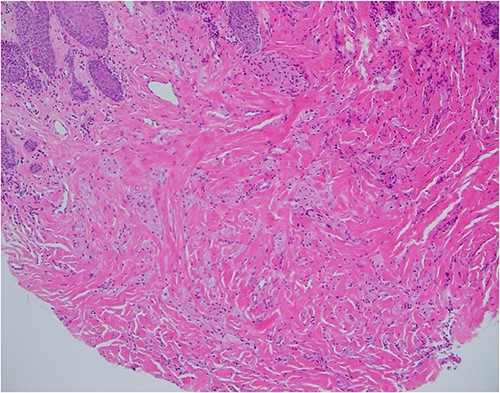

Haematoxylin and eosin stain, 100× magnification, showing tumour cells in stroma that may not be sampled by a superficial biopsy.